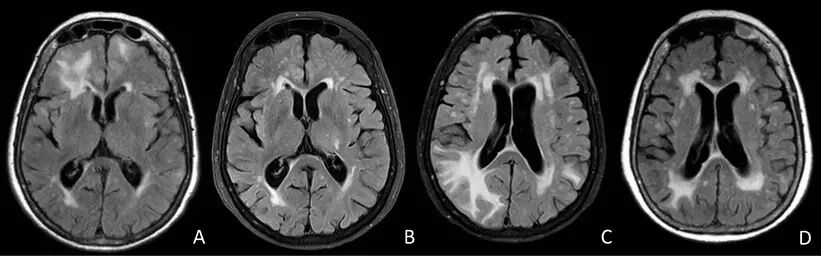

CT平扫可提示皮质下广泛低密度病灶,通常累及颞叶或额叶。几乎所有患者的MRI均异常,主要表现为T2或FLAIR上单发或多发的白质高信号,可伴水肿,病灶常为非对称性,可散在分布或融合成片或呈肿瘤样伴占位效应,灰质较少累及T2*WI上绝大多数患者存在皮质-皮质下微出血,部分患者皮质-皮质下既有微出血又有大出血,只有少数患者表现为大出血。约50%患者有脑白质疏松表现,50%患者有脑膜轻度增强。脑血管造影可见约22%患者存在轻度的双侧脑血管狭窄,主要是大脑中动脉、大脑前动脉的小分支。

(80岁女性,表现为全面性癫痫发作和波动性右侧轻偏瘫。A:FLAIR上可见右侧额叶大片皮质下高信号;B:4月后复查病灶消失;1年后患者出现快速进展性遗忘型认知功能障碍。C:FLAIR上可见顶叶新病灶;D:3月后复查病灶消失